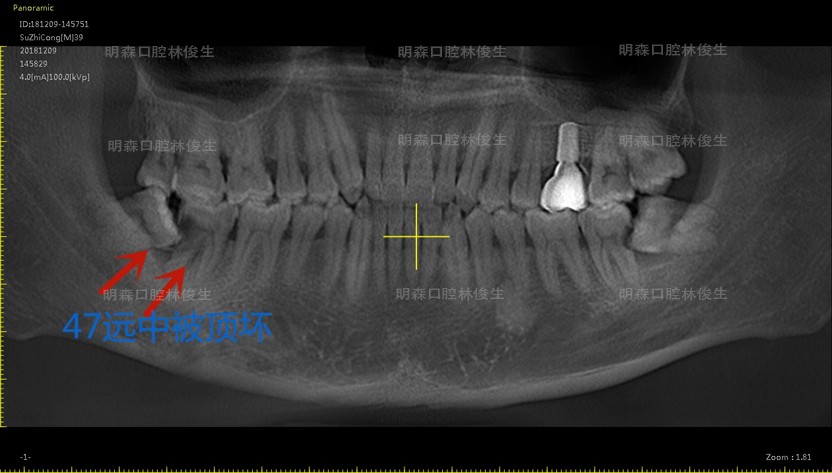

智齿发炎不拔会带来什么后果?我遇到这样一位患者他下颌47远中被智齿“吃了一小块”,导致口腔反复发炎,最后智齿与被“吃了一块”的邻牙一并拔除,最终患者只能通过做种植牙恢复咬合功能。

由于智齿的生长位置、大小、形状的不同,对口腔造成的局部炎症反应或机械性损伤都不尽相同,具体我以本次接诊的患者病症为例。

该患者属于远中阻生齿,牙冠向远中(下颌升支方向)倾斜挤压到正常的邻牙,容易引发智齿冠周炎以及领面龋,主要症状包括智齿周围软组织的肿胀、疼痛、糜烂及脓液分泌,导致食物嵌塞造成邻面龋,症状严重者甚至会因阻生齿引起邻牙远中骨吸收,形成牙周袋,诱发牙周炎。